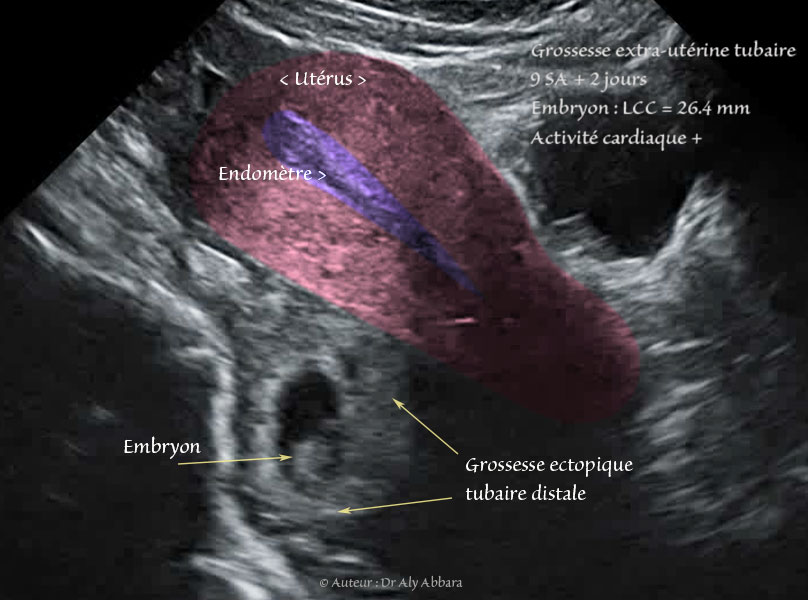

Grossesse extra-utérine tubaire distale évolutive âgée de 9 SA et 2 jours : activité cardiaque positive ; mouvements actifs positifs ; longueur craniocaudale égale à 26,4 mm

• Séquences vidéos (type *.GIF) d'une exploration échographique par voie transpariétale (coupe sagittale médiane sur l'utérus) mettant en évidence la présence d'une grossesse extra-utérine tubaire distale évolutive âgée de 9 SA et 2 jours :

• Sur d'autres coupes, on observe la présence d'un important épanchement intra-péritonéal atteignant l'espace de Morison. En per-opératoire, cette hémorragie intra-péritonéale a été évaluée à 1 300 ml.

Il s'agissait d'une grossesse extra-utérine tubaire droite en voie d'expulsion par un avortement tubo-abdominal.

• Ce sac gestationnel ectopique tubaire droit est associé à un tableau clinique caractérisé par la présence d'une douleur pelvienne intense et constante, sans métrorragie.

• Biologie : le dosage de β-hCG plasmatique était égal à 4 800 UI/l.